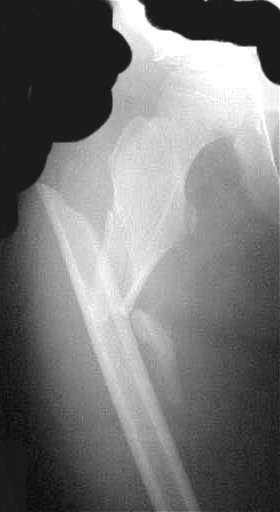

Regarding pediatric femur fractures, I am wondering how would the members address this comminuted subtrochanteric fracture in 9 years old girl, 34 kg weight, with opposite tibial spine avulsion in stable medical condition?

Unfortunately, I have not digitalize the posted x-rays perfect. My intention was not to trick anybody, I was pretty sure that we have what I have described - comminuted subtrochanteric fx not involving trochanteric region. Also, in my operating room I have always all options available in case that I have to switch the gears.

This is a done case. I thought that trochanteric entry point is potentially too risky (see Ch. Mehlman and my discussion from before). Bridge plate with screws going into the neck is definitively the option (as you can see it from this case with fx extended proximally to the lesser trochanter, the first one which I have done for pediatric femur fractures).

This patient had 110 degrees hip dynamic screw put in (regular, flat radiolucent table). Although I felt necessary to put the cerclage wire for better reduction, that was done with minimal additional damage and I would still consider it as "bridge plating technique" (the scar length is not crucial determining factor). She was weight bearing as tolerated after 6 weeks (without crutches) and x-rays presented here are after 8 weeks.